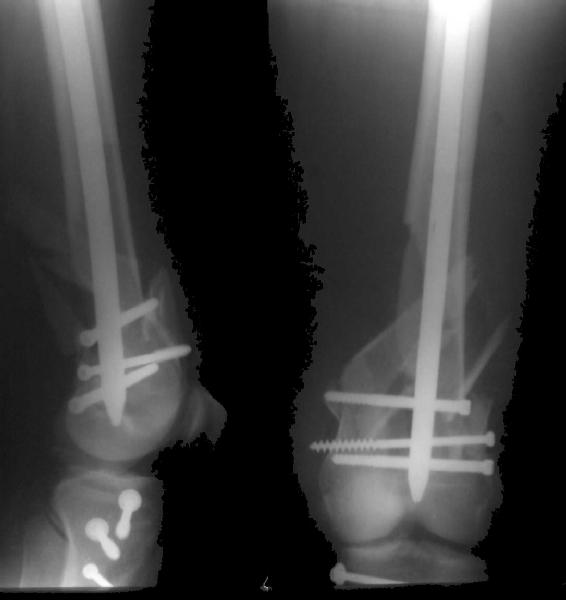

This is what we have done... As generally true for LISS look at the bone not the hardware.

There are two more srews above. The one not completely in got damaged head.

Look what we would have done.